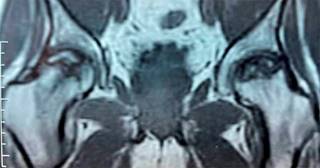

Figura 2: Resonancia magnética nuclear con imagen de necrosis de cabeza femoral sin colapso de la superficie articular.

Todos los pacientes habían recibido corticosteroides como parte de su régimen de tratamiento para COVID-19 con dosis promedio de 480 mg, en un rango de 400 a 1,200 mg de hidrocortisona (o su equivalente -se adjunta Tabla de conversión-) (Tabla 1). Estos pacientes mostraron síntomas clásicos de NAVCF caracterizados por un rápido deterioro funcional con sintomatología clínica de dolor, limitación a la carga y movilización. Asimismo, presentaron los cambios correspondientes en las imágenes de radiografías y resonancia magnética nuclear (RMN); los estadios de necrosis fueron clasificados según Ficat8 (Figuras 1 y 2). Se incluyeron estadios I a III de la clasificación dada la juventud de la serie y que no tenían artrosis con disminución del espacio articular.